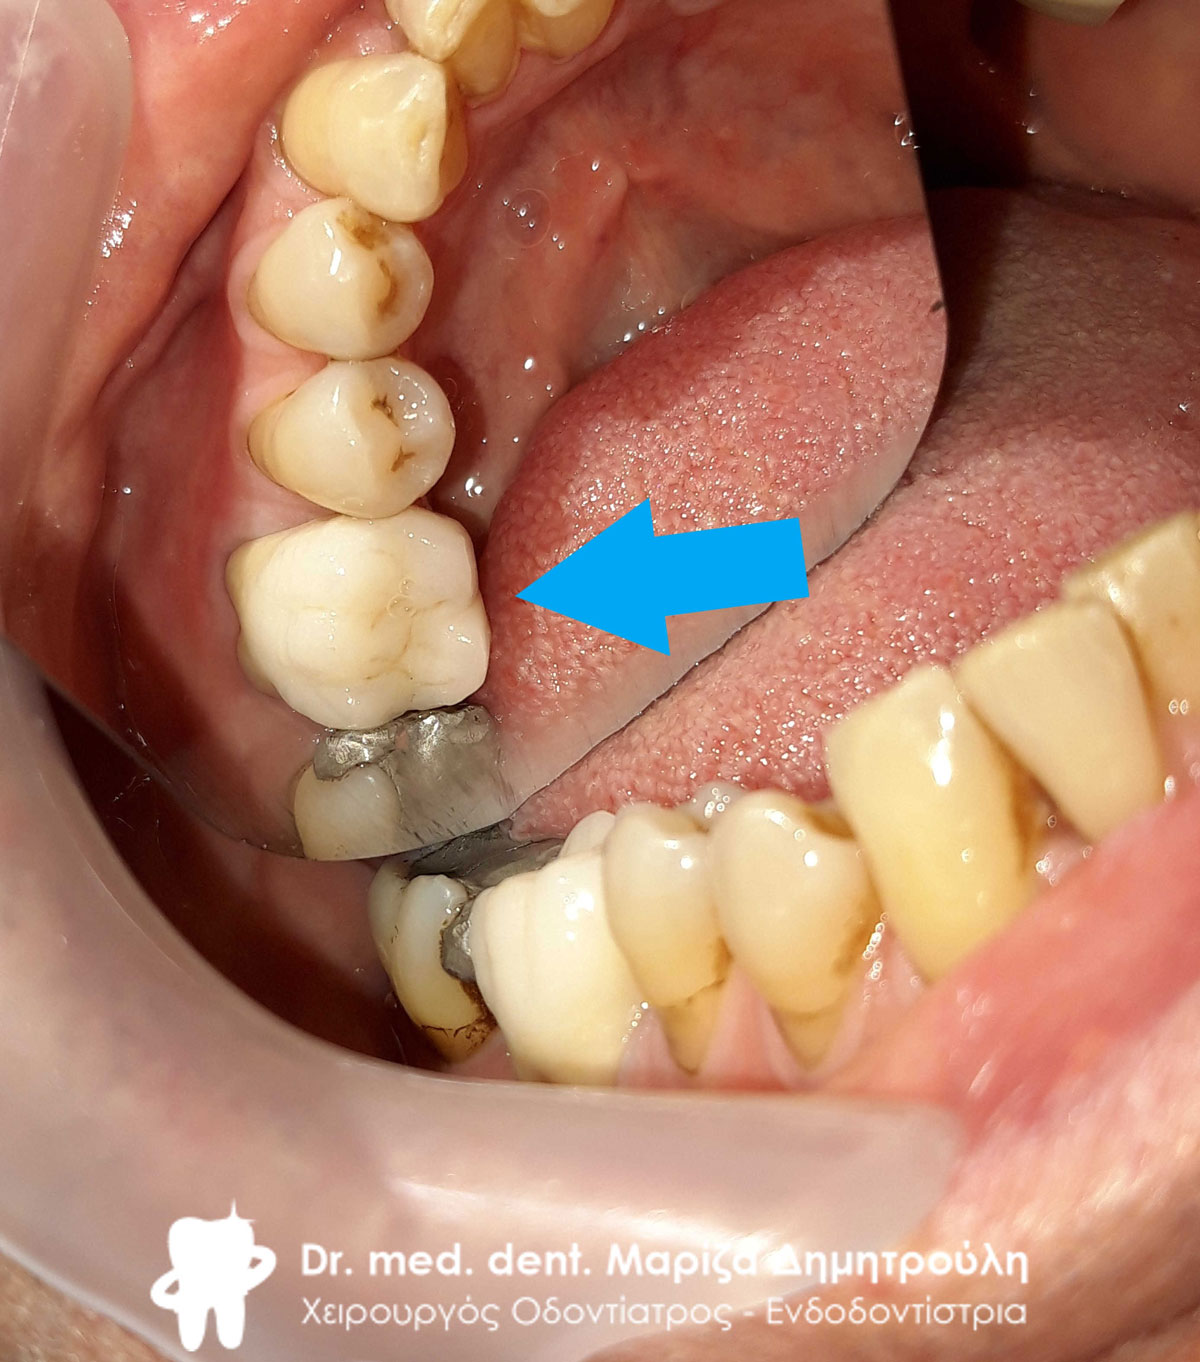

Περιστατικό – Ολοκεραμική θήκη ζιρκονίου στην αριστερή πλευρά της κάτω γνάθου

Η ασθενής είχε ένα απονευρωμένο δόντι, το οποίο της είχε προταθεί να προστατευτεί με θήκη προτού σπάσει. Η ασθενής αμέλησε τις οδηγίες του οδοντιάτρου με αποτέλεσμα το δόντι να σπάσει μετά από 6 μήνες. Παρόλα αυτά υπήρχε ακόμη η δυνατότητα διατήρησης του δοντιού στο στόμα, εφόσον βέβαια αυτό καλυπτόταν με ολοκεραμική θήκη. Αρχικά το δόντι ανασυστάθηκε με άξονα υαλονημάτων, λήφθηκαν αποτυπώματα και ο οδοντοτεχνίτης κατασκεύασε ολοκεραμική θήκη ζιρκονίου.

“Τελευταία στιγμή” η ασθενής έσωσε το δόντι. Αν είχε ακολουθήσει τις οδηγίες του οδοντιάτρου θα είχε αποτραπεί το σπάσιμο του δοντιού.

ΠΡΙΝ

Ενδιάμεση κατάσταση μετά την ανασύσταση του δοντιού με άξονα υαλονημάτων

ΜΕΤΑ